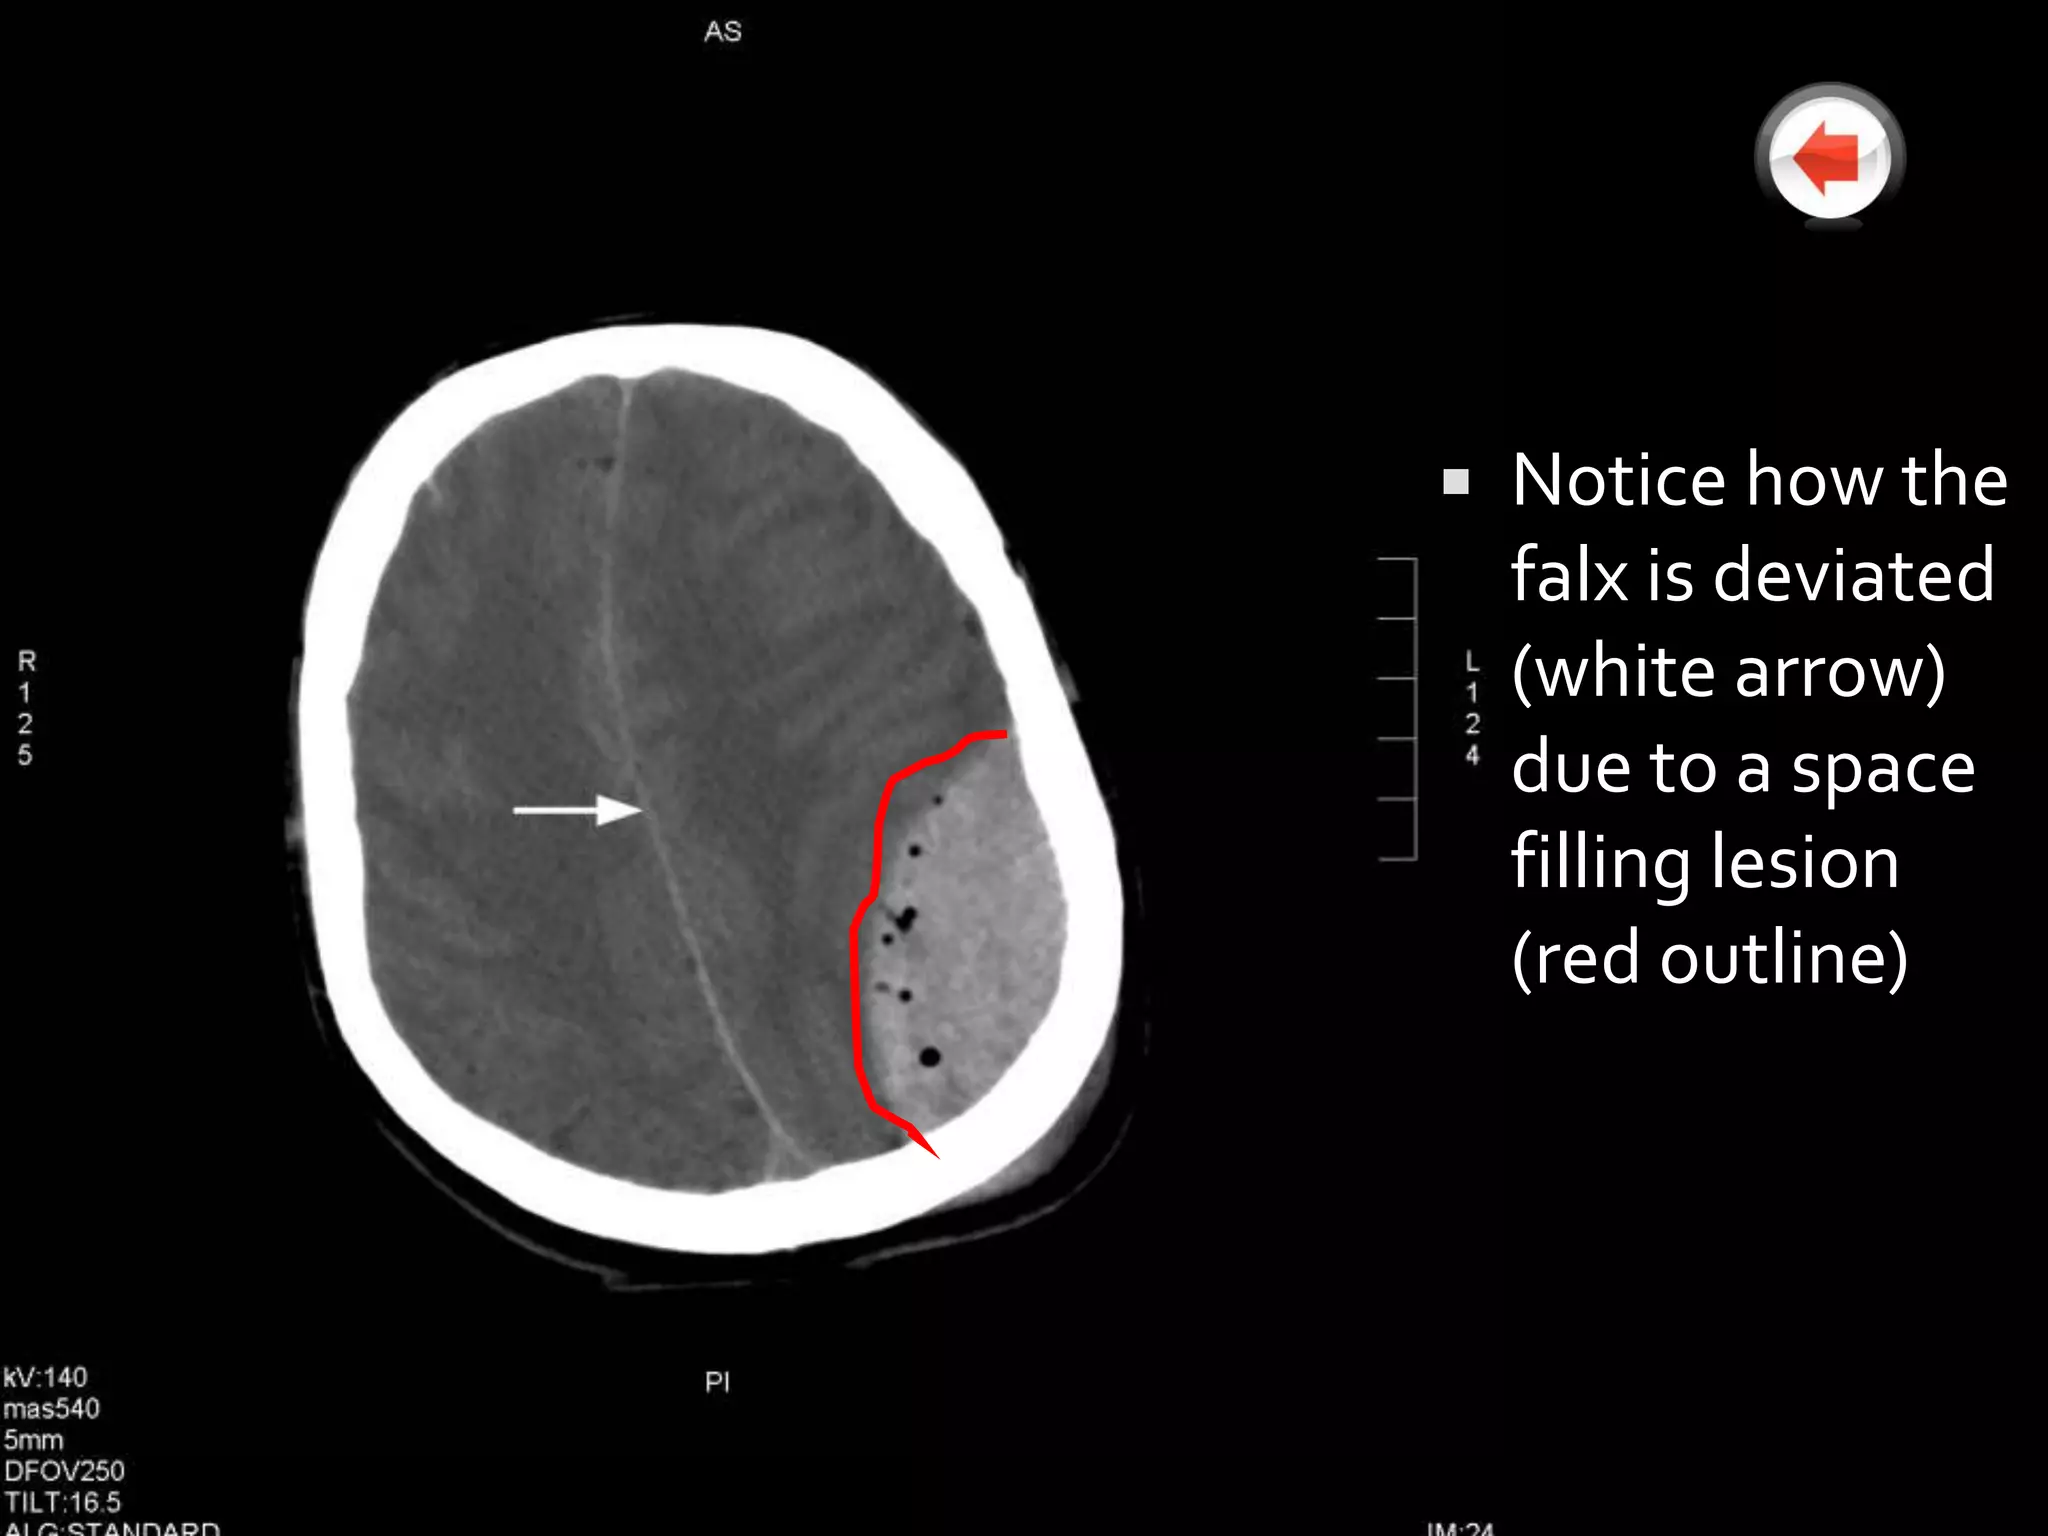

   Notice how the

falx is deviated

(white arrow)

due to a space

filling lesion

(red outline)